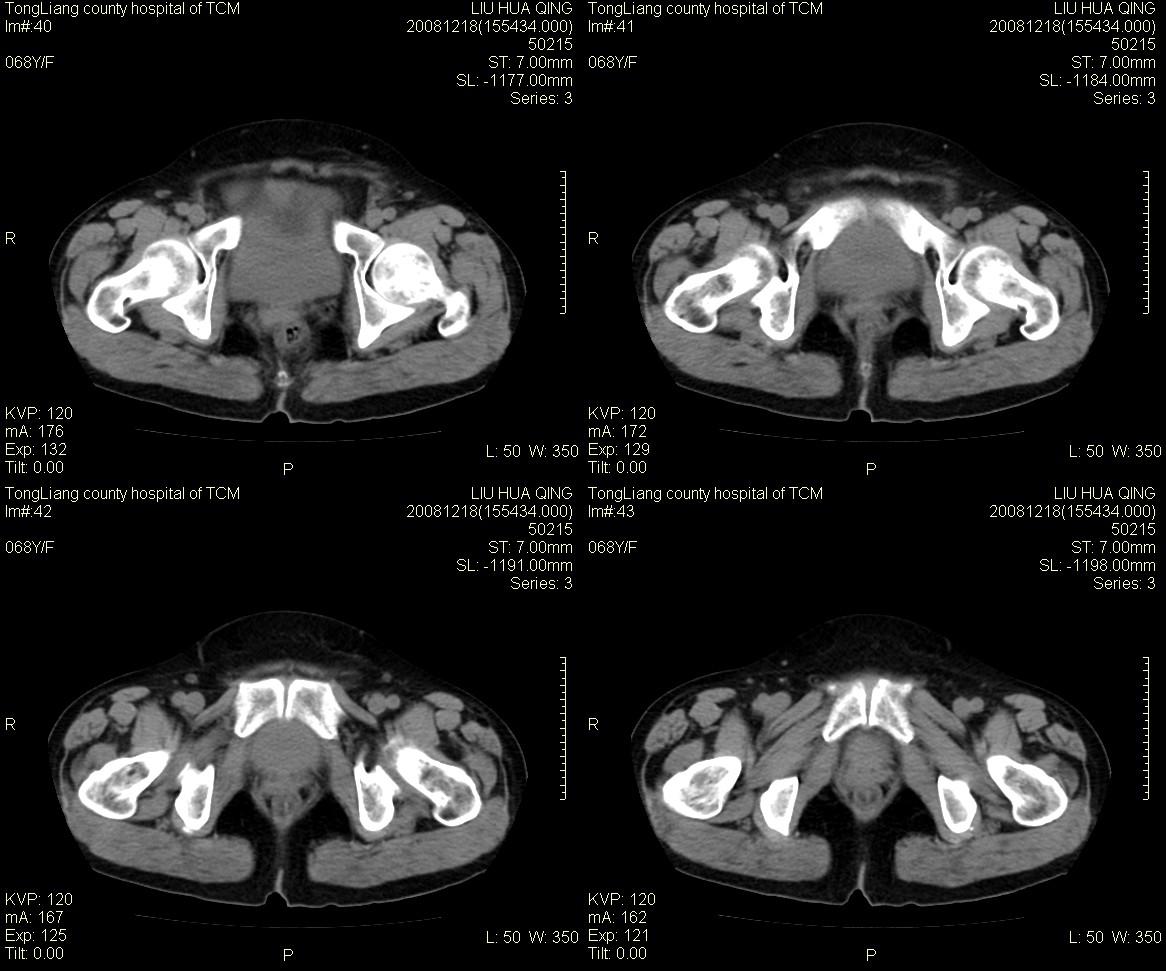

女,68y,下腹疼3月,一月半前院外ct示上腹未见异常。近1月来,症状加重。4天前入院,b超示胸腹水。今日呕吐频繁。  生化检查:  结核抗体阴性,血沉18mm/h, 癌胚抗原阴性,胸水细胞学检查见多数淋巴细胞。 白细胞总数5.4x10^12/l,血红蛋白104g/l.

腹腔积液可以肯定,原因?右侧下腹肠壁增厚,周围脂肪密度增高,粘连坏死?---梗阻坏死(不像)还是血栓坏死,占位?期待结果。

1)右侧腹腔前部见类似“网膜饼”样改变,考虑网膜转移瘤。2)腹水。

腹膜污染[大网膜增厚可见污垢征及小班结与饼片影,肠系膜增厚],大量腹水。考虑癌性腹膜炎,建议查腹水。结核待排.注意上腹部及胃肠道检查